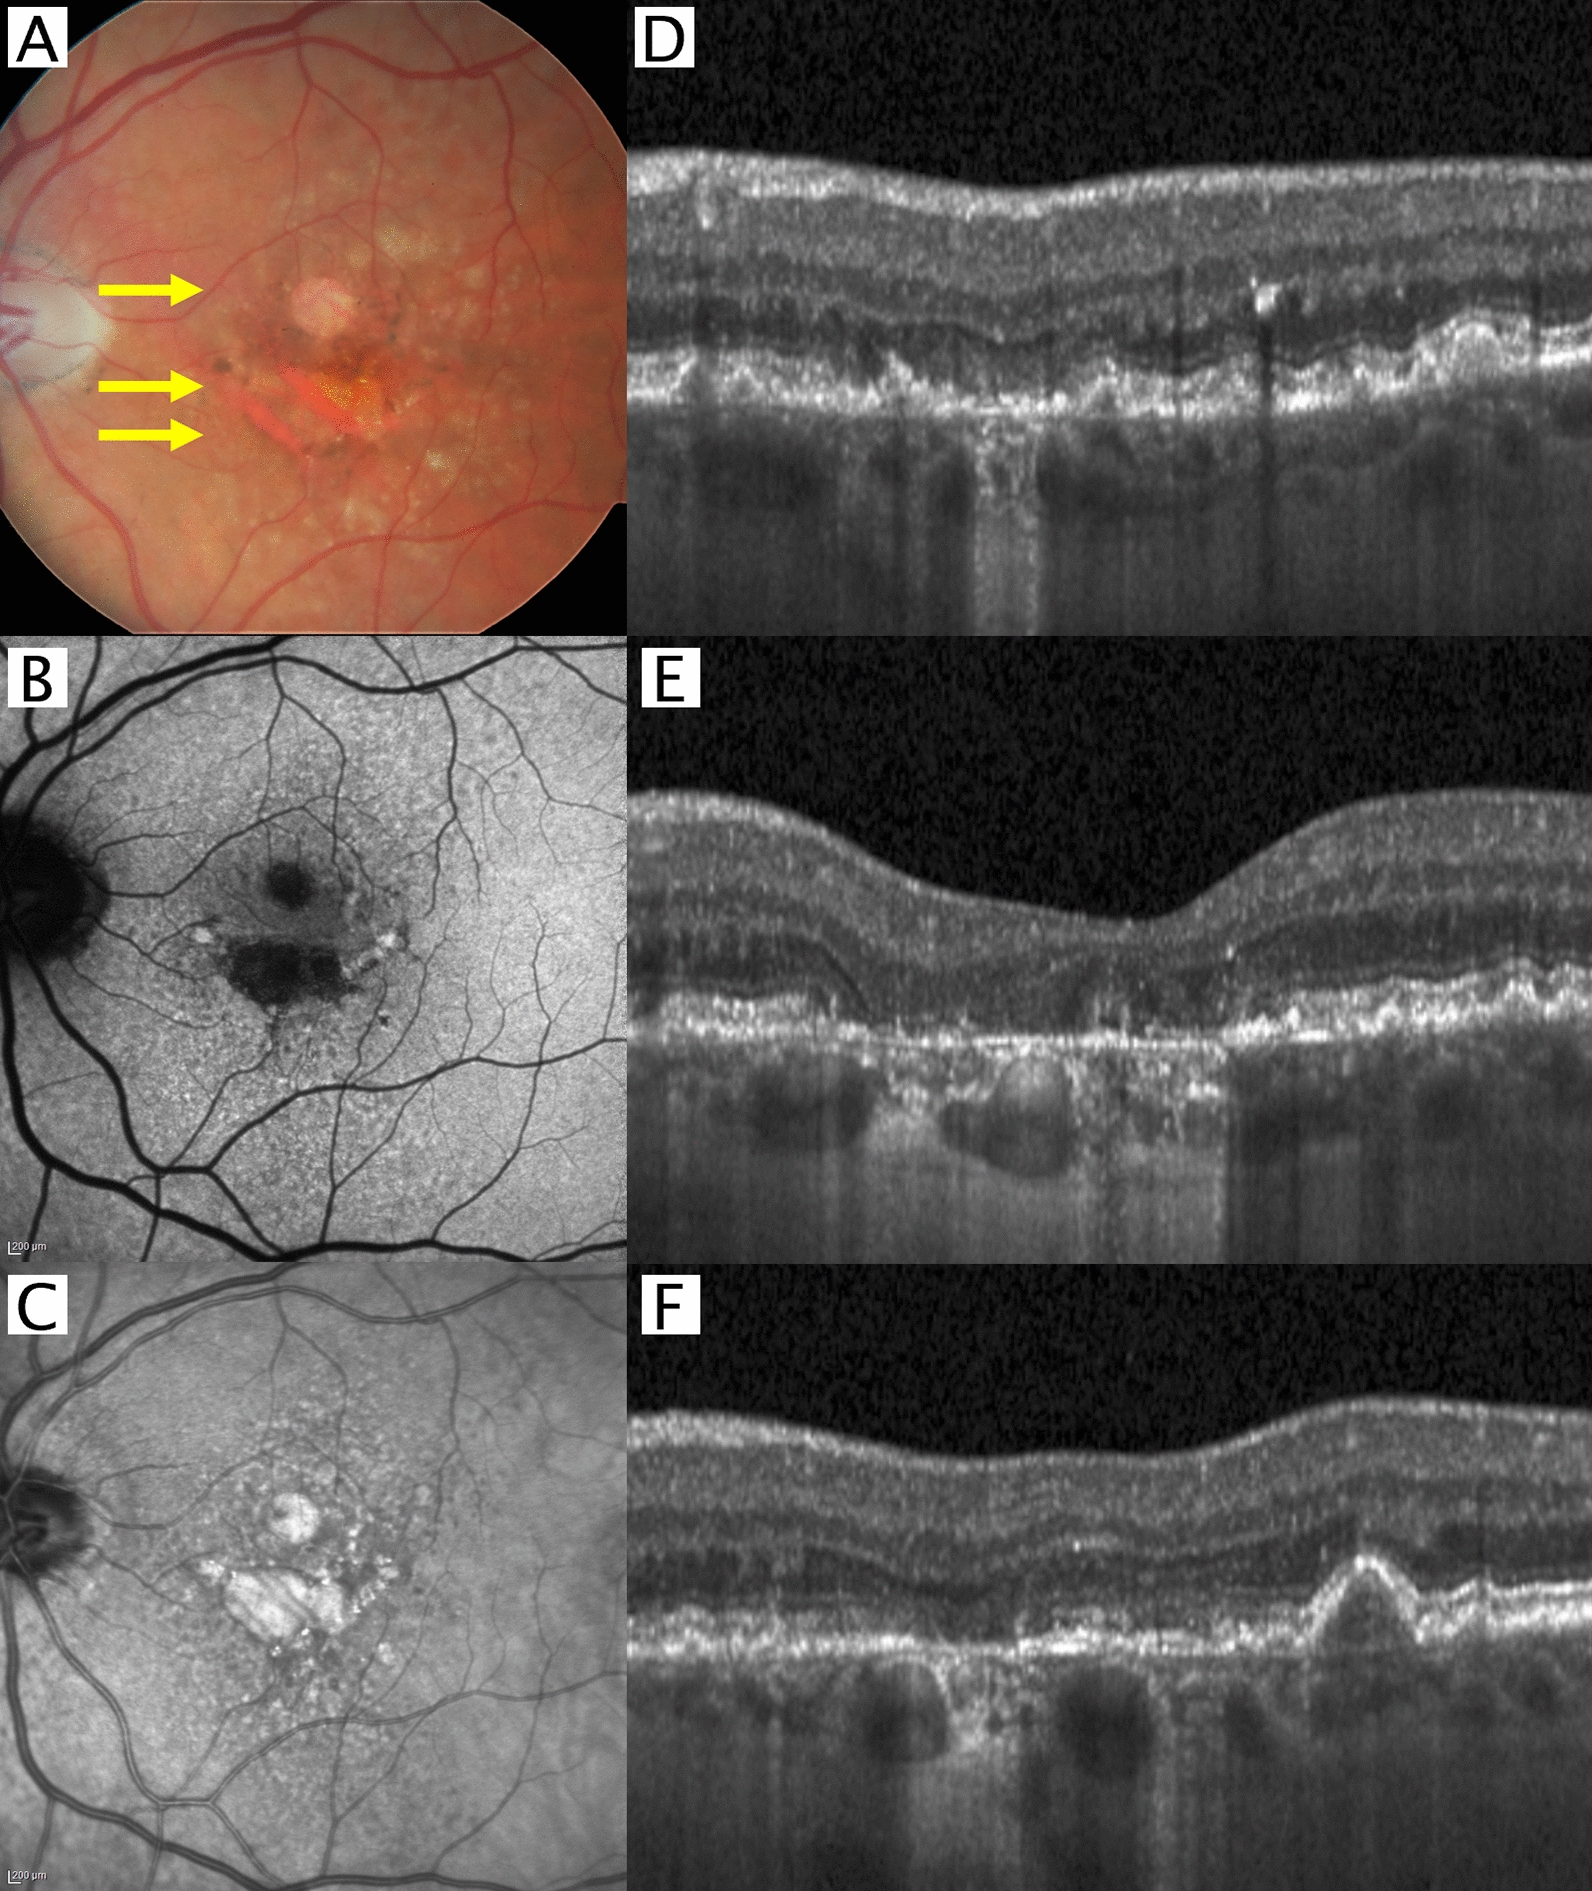

Conventional CFP was established as one of the first ways to diagnose and monitor AMD and the progression of GA. Its advantages are its wide availability and cost-effectiveness for screening and documentation. In addition, because it was one of the first ways to document GA, there are large datasets available to support its use in the development of artificial intelligence algorithms [18, 19]. GA on CFP appears with sharp demarcated areas of atrophy that highlight increased visibility of the choroidal vessels (Fig. 1A). Additionally, it allows for visualization and differentiation of drusen, deposits and other features associated with a different risk for GA progression, providing prognostic information [20]. Conventional CFP typically covers the central 30° area, with a seven-field early treatment diabetic retinopathy study (ETDRS) standard CFP covering approximately 75°. Newer approaches and devices can cover up to 200° of the retina, allowing for ultra-wide field imaging [21]. Features of AMD may also affect the peripheral retina [22].

Major imaging modalities in a patient with geographic atrophy (GA) secondary to age-related macular degeneration (AMD). A Color fundus photography (CFP), B 488 nm wavelength fundus autofluorescence (FAF), C) Near-infrared reflectance (NIR) imaging, D-F) Optical coherence tomography (OCT) B-scans at the level indicated by the three yellow arrows in A

Fundus autofluorescence (FAF) imaging uses the excitation of fluorophores within the RPE (mainly lipofuscin and melanolipofuscin) and generates an image on the basis of the autofluorescent emission of light reaching the imaging device. Loss of the RPE also results in the loss of fluorophores within the RPE, explaining the hypoautofluorescent appearance of a lesion on FAF. The most used FAF is blue-light FAF (BAF), which uses light at approximately 488 nm. BAF has been routinely used in clinical trials and the area of atrophy can be quantified with software, such as the RegionFinder [5, 6]. However, the blue light is blocked by macular pigment and the involvement of the fovea is often difficult to distinguish (Fig. 1B). Using light in the green spectrum (around 532 nm) or near-infrared (around 787 nm) changes the attracted fluorophores and shift more toward melanin [23, 24].

Near-infrared reflectance (NIR) imaging uses tissue reflectance to create a two-dimensional image, often acquired simultaneously to an OCT volume (Fig. 1C–F) [3]. Owing to its longer wavelength in the infra-red spectrum, the signal can penetrate well even in the presence of cataract and deeper into the choroid in comparison to shorter wavelength. While GA appears hypoautofluorescent on FAF, it appears hyperreflectant on NIR owing to decreased signal blocking from the missing RPE with increased reflection from the underlying tissue. Studies have shown good overlap between GA measurements on NIR compared with FAF [33].